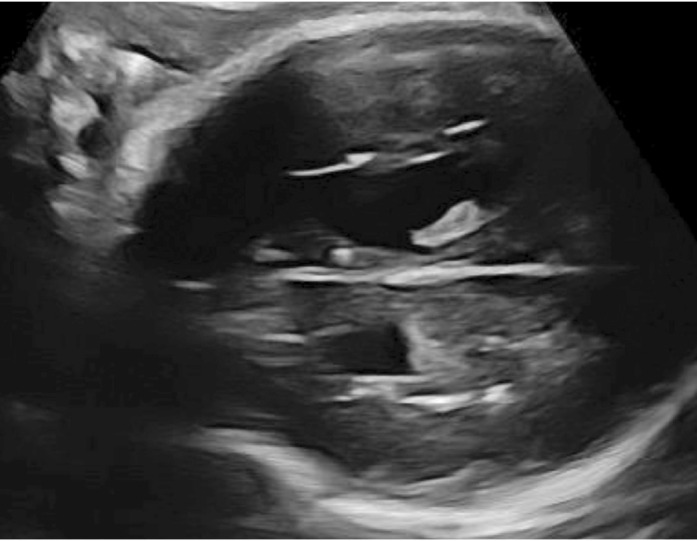

Results: During the study period, a total of 49,292 toxoplasma IgM tests were examined. Fifty pregnant women whose toxoplasma IgM was positive with a low-anti-toxoplasma IgG avidity index were enrolled in the study group. Forty percent of the pregnant women are expected to have amniocentesis. There was only one termination of pregnancy with specific ultrasonographic findings. Toxoplasma PCR was found to be negative in the other pregnant women. Of the pregnant women who were followed up, 23 gave birth in our hospital and the Sabin Feldman test was positive in 65.2 percent (15/23) of the newborns.

Conclusion: Antenatal toxoplasmosis screening should be preserved for pregnant women with fetal ultrasonographic findings which may be related to toxoplasmosis. Further studies are needed.